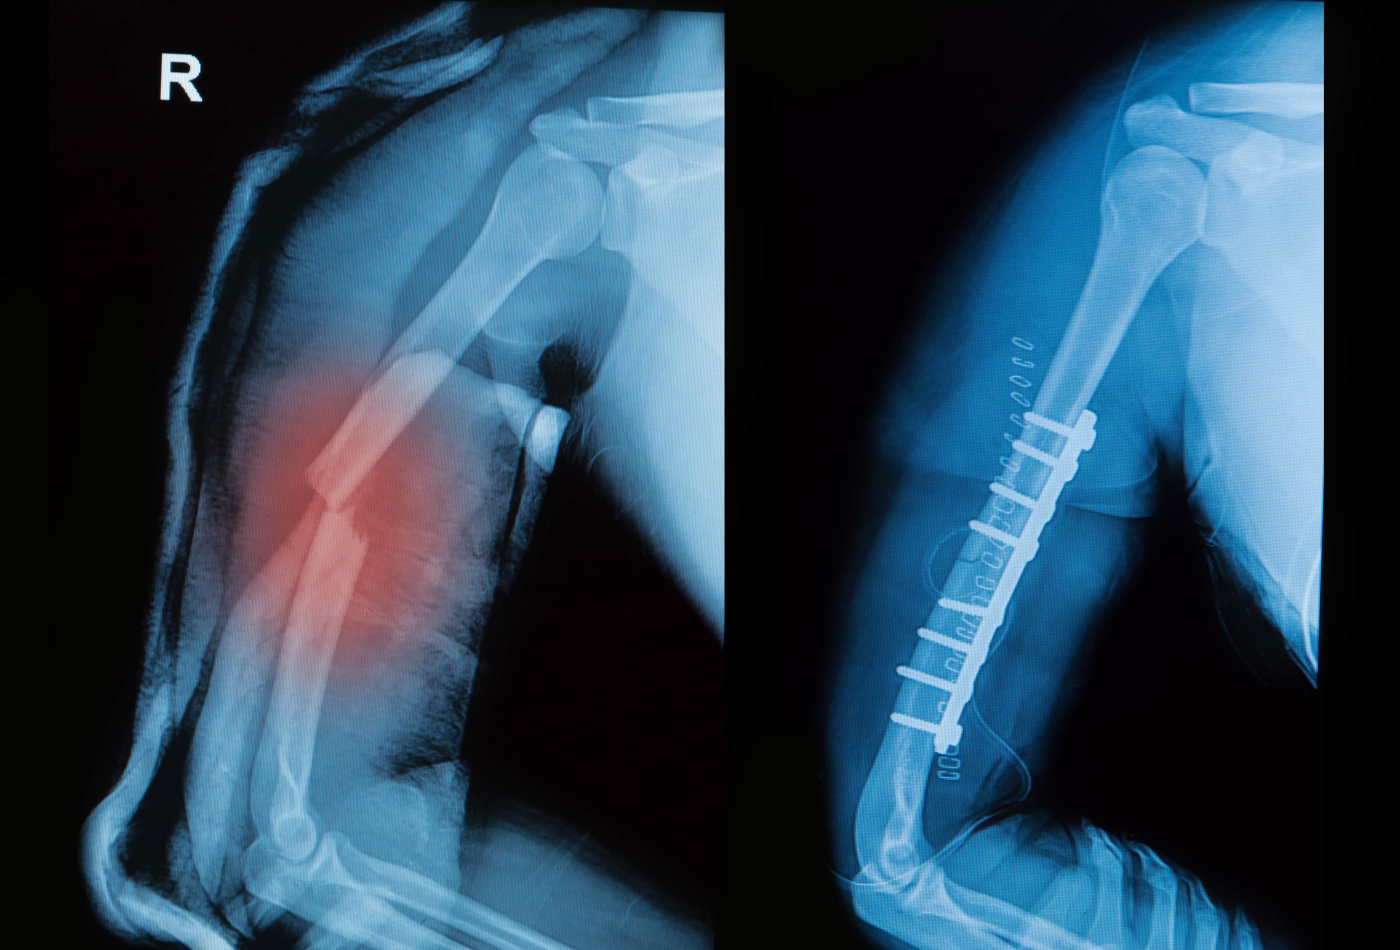

How is an arm fracture diagnosed?

The doctor will examine the arm to detect any pain, swelling, deformation or open wounds. After discussing the symptoms and causes of injury, an x-ray may be required to determine the location and severity of the fracture. Other imaging diagnostics such as magnetic resonance imaging (MRI) may be recommended for a more detailed look.

Most fractures will need to have a splint or partial cast applied to stabilise the broken bones. Some fractures, especially in the upper arm and shoulder, may only need to be immobilised in a sling.

- Complicated fractures that have multiple breaks points, involving the joints or are unable to be stabilised in the emergency department or doctor’s office.

Most cases of arm fractures do not require hospitalisation. For all other types of fracture, the doctor might refer you to an orthopedic (bone specialist). The orthopedic surgeon will then determine the next course of action (continue to apply a splint, a cast or undergo surgery) depending on the type of fracture.